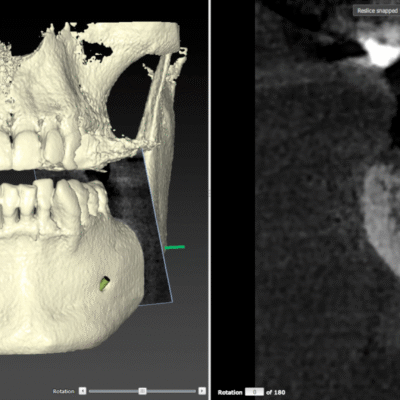

L’implantologie est dédiée à la pose d’implants dentaires qui remplacent les dents manquantes de manière durable et esthétique. Dr Karima Rahmani utilise des technologies de pointe pour planifier et réaliser des interventions précises, assurant une intégration parfaite des implants. De la greffe osseuse à la pose de prothèses sur implants, chaque étape est conçue pour offrir une solution fiable et esthétique, rétablissant la fonction et l'apparence de votre sourire.

- Pose d'implants dentaires

- Greffes osseuses

- Régénération osseuse guidée

- Planification 3D